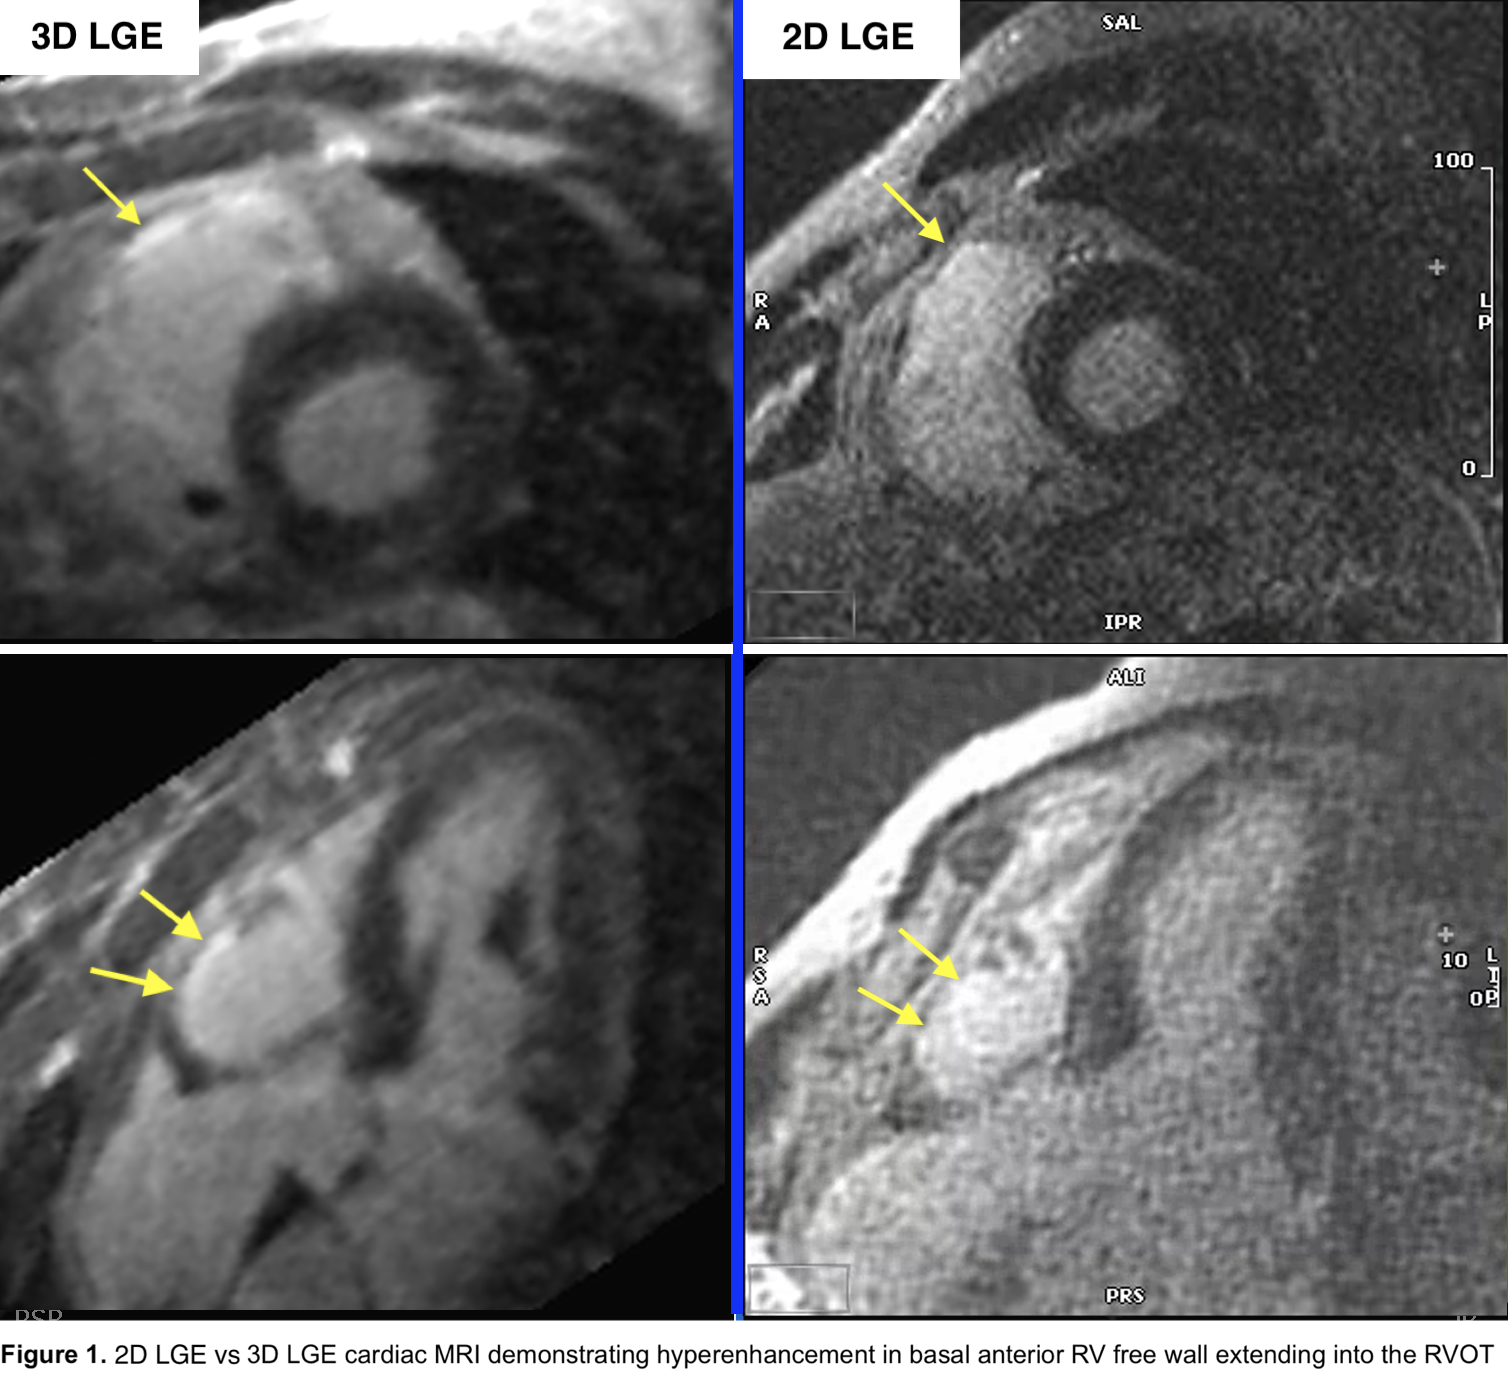

Figure 2. Comparison of 3D LGE and electroanatomic mapping (EAM) of the right ventricle with corresponding intracardiac electrograms at the RVOT, with long and fractionated late potentials (red arrow) before and after ablation. Left panels show 3D LGE-derived scar visualization (yellow arrows). Middle and right panels show corresponding voltage maps with and without ablation lesions (green tags).png)